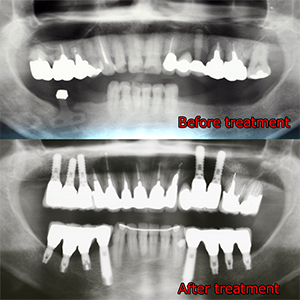

治療後16年経過

このケースがどうして16年経過しても、治療終了時と大差なく状態を維持できているかというと、ズバリ「定期的なメインテナンス」の一言に尽きます。

もし、3カ月に一度、メインテナンスに来院されていなければ、間違いなく再度新たな治療介入が必要になっていたことでしょう。これは、疑いの予知はありません。

メインテナンス時に行うことは、PMTCと咬合調整が主体です。また、1年に一度のレントゲン撮影を行い、骨レベルの変化やその他の問題が無いかの確認をします。

16年治療介入の必要なく、過ごしてこられたのは、きちんとメインテナンスに来院されたことが主たる要因です。

長期的な予後を左右するものは、ズバリ定期的なメインテナンスが鍵と言わざるを得ません。

皆様も歯を入れたら終わりではなく、治療を終えたら、定期的なメインテナンスをお受けになることをおすすめいたします。『メインテナンスは、歯医者が金儲けですすめている!』といった言葉を良く耳にしますが、決してそうではありません。メインテナンスを行わず放置してしまうと、必ず治療介入を強いられることになります。それは再度多額の治療費が発生する事態となり、そちらの方が歯医者にとっては、金儲けになります。しかし、我々は金儲けで歯科医業を営んでいる訳ではないのです。